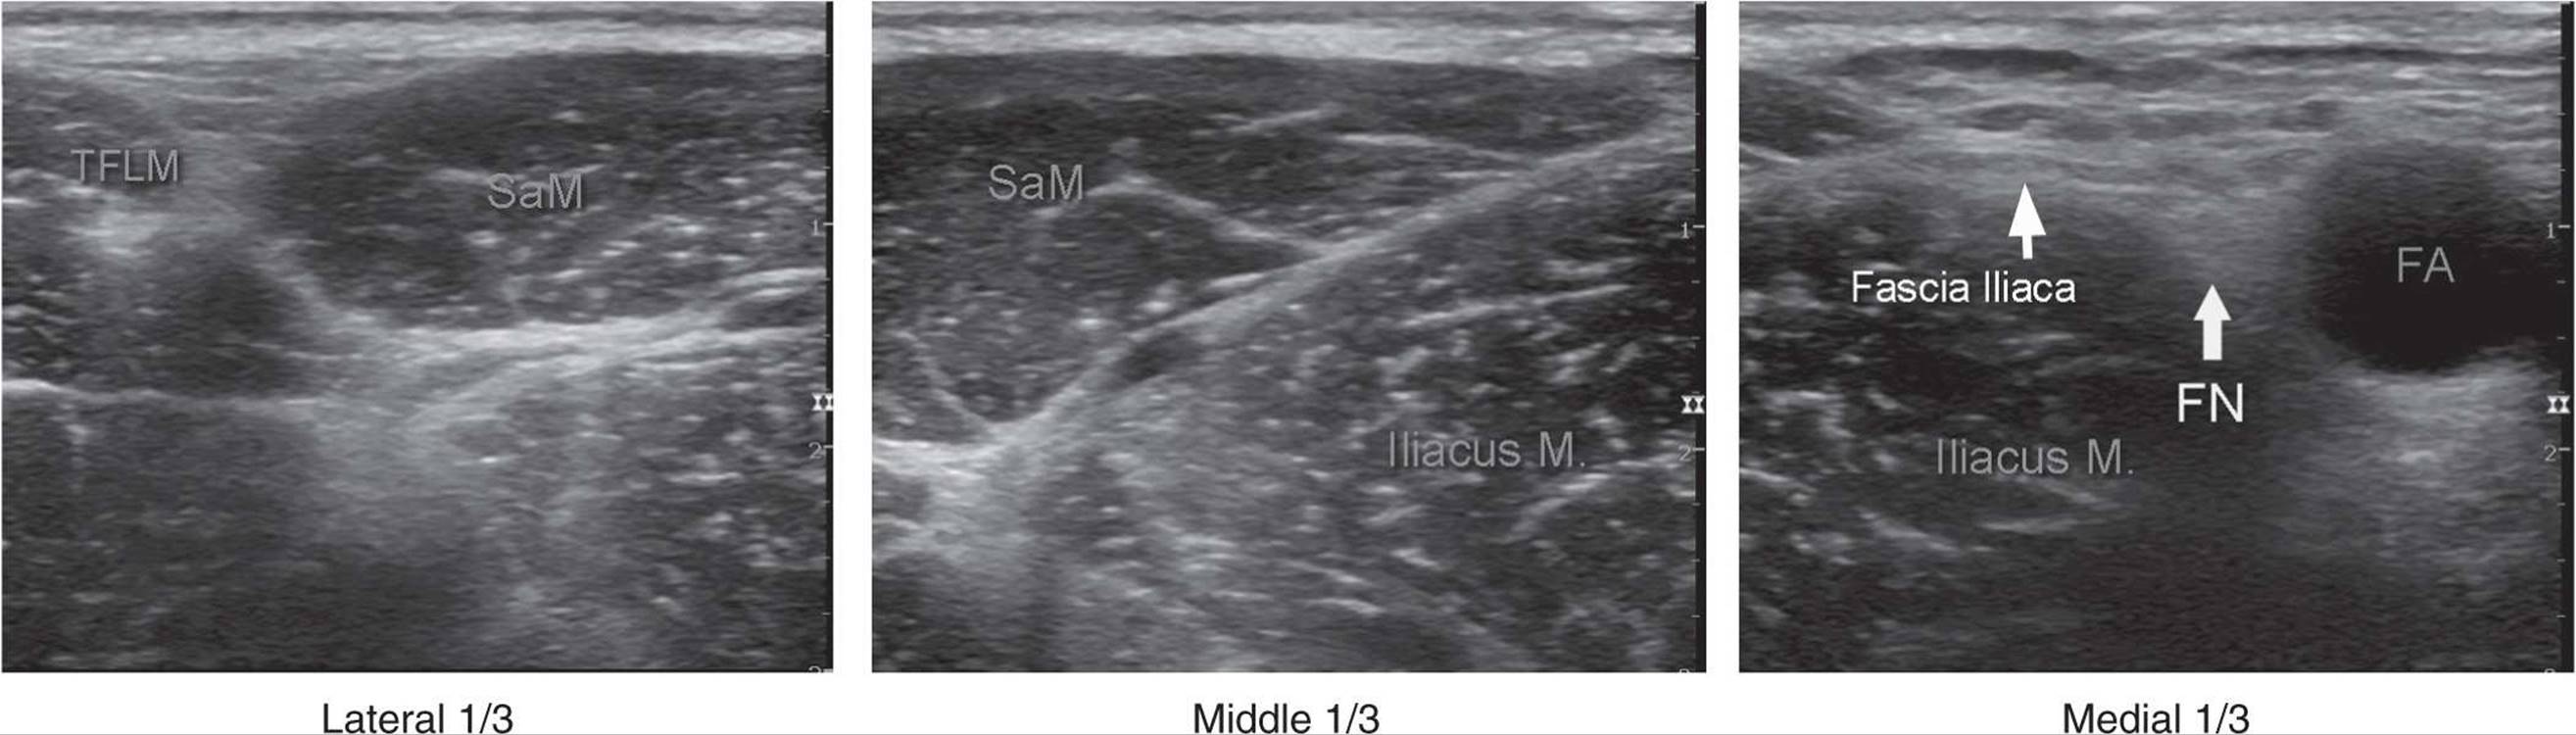

The fascia iliaca is located anterior to the iliacus muscle (on its surface) within the pelvis. It is bound superolaterally by the iliac crest and medially merges with the fascia overlying the psoas muscle. Both the femoral nerve and the lateral cutaneous nerve of the thigh lie under the iliacus fascia in their intrapelvic course. Anatomic orientation begins in the same manner as with the femoral block: with identification of the femoral artery at the level of the inguinal crease. If it is not immediately visible, sliding the transducer medially and laterally will eventually bring the vessel into view. Immediately lateral and deep to the femoral artery and vein is a large hypoechoic structure, the iliopsoas muscle (Figure 36-2). It is covered by a thin layer of connective tissue fascia, which can be seen separating the muscle from the subcutaneous tissue superficial to it. The hyperechoic femoral nerve should be seen wedged between the iliopsoas muscle and the fascia iliaca, lateral to the femoral artery. The fascia lata (superficial in the subcutaneous layer) is more superficial and may have more then one layer. Moving the transducer laterally several centimeters brings into view the sartorius muscle covered by its own fascia as well as the fascia iliaca. Further lateral movement of the transducer reveals the anterior superior iliac spine (Figure 36-2). Additional anatomical detail can be seen in cross sectional anatomy in Section 7. Since the anatomy is essentially identical, it is not repeated here.

FIGURE 36-2. A panoramic view of ultrasound anatomy of the femoral (inguinal) crease area. From lateral to medial shown are tensor fascia lata muscle (TFLM), sartorius muscle (SaM), Iliac muscle, fascia iliaca, femoral nerve (FN), and femoral artery (FA). The lateral, middle and medial 1/3s are derived by dividing the line between the FA and anterior-superior iliac spine in three equal 1/3 sections.